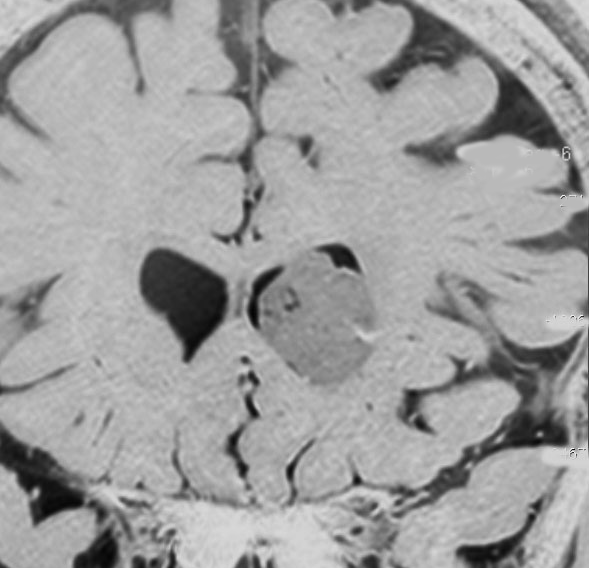

10年観察してもあまり変わらない,数が増えることがある

2012年に偶然発見され,その後,10年の経過観察されました。

2022年のものです,透明中核から出たものは少し大きくなっています。他にも数個の小さな腫瘍が脳室上壁にあるのですが,なにもしないでほっておきます。